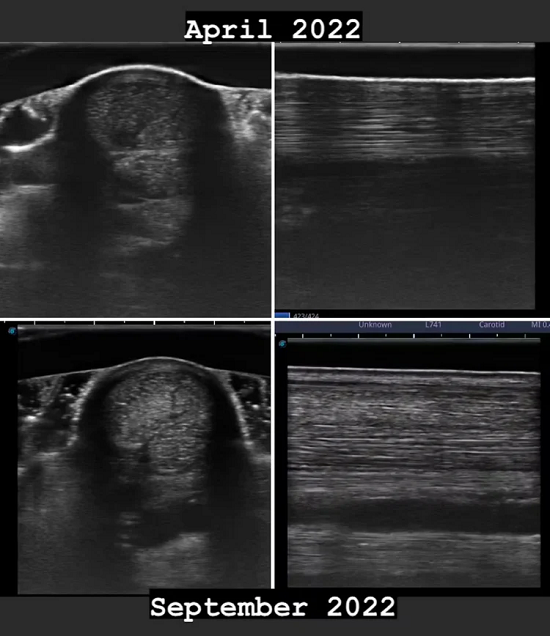

Utrolige resultater! "Kunne ikke helt tro, hvor genialt dette var til at hjælpe med helingen af seneskader. Dylagen, der scannede en af mine, pa tidspunktet for skaden og igen 6 máneder senere var overrasket over, hvor stor en forskel TendonX gjorde. |